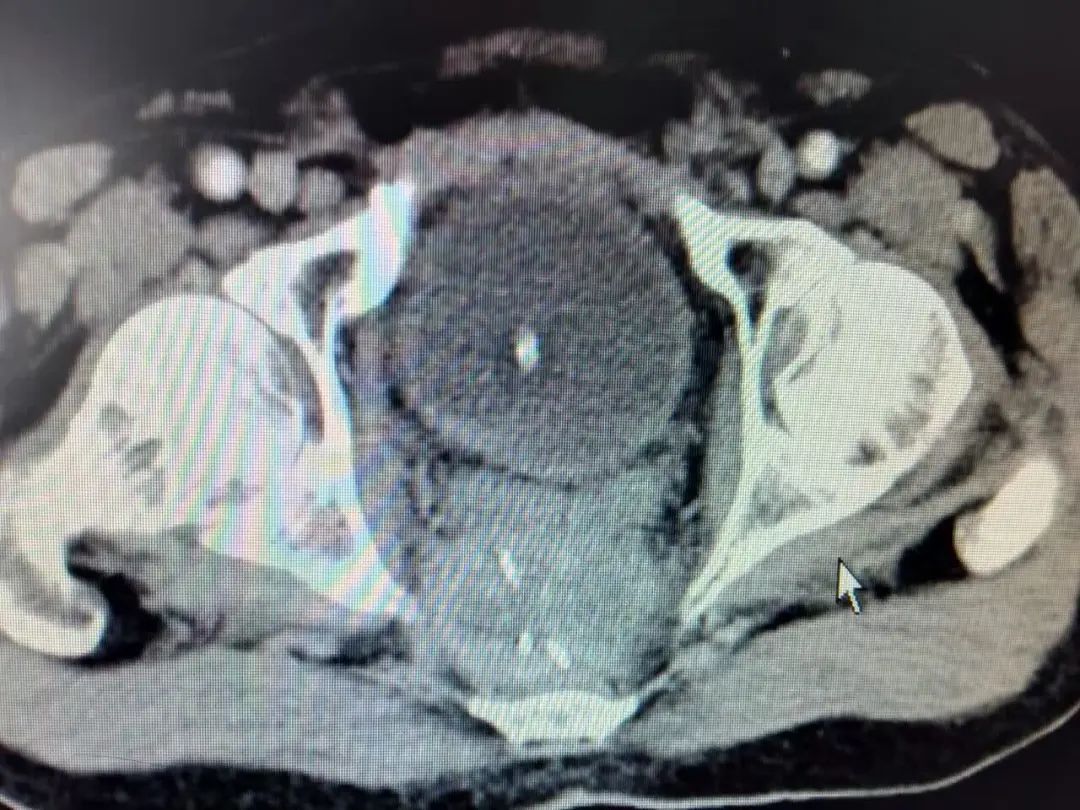

▲该患者为直肠癌术后骶前复发,疼痛难忍,放射性粒子植入是一个很好的挽救性治疗手段。